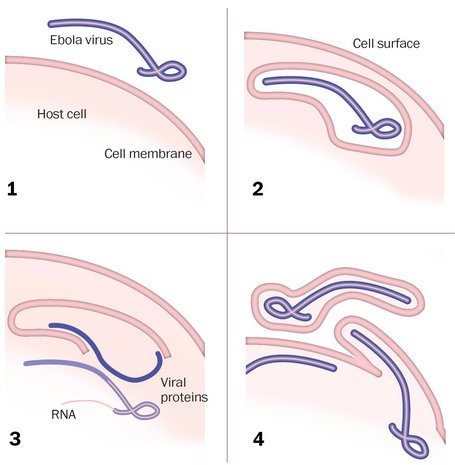

استراتژی تهاجم سلول

۱. ویروس به سطح سلول می چسبد، در آن وارد شده و توسط غشای سلولی احاطه می شود.

۲. پروتئین هایی که جهش سلول را پوشش می دهند غشا را باز کرده و اجازه می دهند RNA ویروس وارد سلول شود و شروع به همانندسازی کند.

۳. نحوه خروج از سلول به طور کامل درک و شناخته نشده است، اما به نظر می رسد که ذرات ویروس در سطح سلول جمع شده و بیرون می آیند و ممکن است با یک پاکت میزبان خارج شوند.